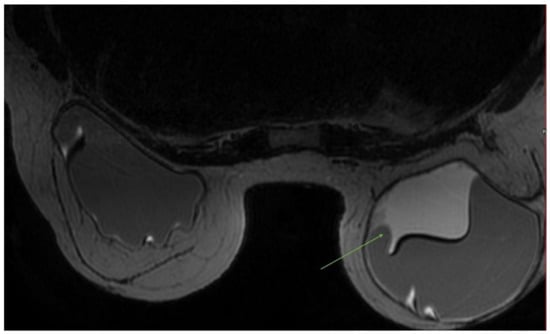

| MRI | Breast implants show different intensity signals due to their composition: -Silicone single lumen has an intermediate-to-high signal on T2W images, a high signal on the silicone-specific sequence, and a loss of signal in the silicone suppressed sequence; -Saline, single lumen has a high signal on T2W images; -Standard double lumen (outer saline, inner silicone); -Reverse double lumen (outer silicone, inner saline). A fibrous capsule hypointense in all sequences and a small periprosthetic fluid amount are paraphysiological findings. | Acute complications: -Hematoma —hyperintense on T1W images, decreasing over time; -Seroma—intermediate-to-hyperintense on T2W images; -Abscess—fluid collection with irregular, thick peripheral enhancement; -Ancillary signs—edema, skin thickening, and adenopathy. Late complications: -Capsular contraction—prosthetic contour alterations, peripheral enhancement; -Intracapsular breast implant rupture (uncollapsed rupture “keyhole sign”, minimal collapse “subcapsular line sign”, and partial-to-full collapse “linguine sign”); -Extracapsular breast implant rupture; -Rare, breast implant-associated anaplastic large-cell lymphoma, ALCL (peri-implant collection with an enhancing mass and lymphadenopathy). | Breast magnetic resonance imaging is the most accurate technique to assess prosthetic integrity in the clinical or ultrasound suspicion of rupture, but is not justified as a pure screening examination in asymptomatic women of all ages and with any type of prosthesis. Its parametric nature allows the typing of the content of periprosthetic fluid collections (seroma, hematoma) and, combined with the administration of contrast medium, the detection of periprosthetic neoplastic recurrences or complications (breast implant-associated anaplastic large-cell lymphoma, ALCL). |